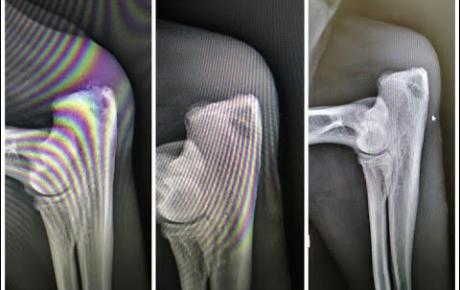

Looking to enhance your treatment options for sports injuries? MLS Laser Therapy might be the game-changer you've been seeking. This innovative and non-invasive approach is revolutionizing treatment, providing athletes with faster recovery times and improved outcomes.

MLS Laser Therapy is a versatile treatment modality that offers a wide range of therapeutic capabilities. Here are some of the versatile clinical uses of MLS Laser Therapy:

Are you curious about the benefits that MLS Laser Therapy can bring to your patients? Cutting Edge is dedicated to finding solutions that can transform your approach to pain. Here are some of the effects you can expect. Read more >> https://t.co/ueVV5EZ8sS

Whether patients are struggling with joint problems, neck pain, arthritis, or other ailments, traditional physical therapy methods don't always provide sufficient relief. MLS Laser Therapy can aid in the treatment for a number of conditions to improve patient outcomes.